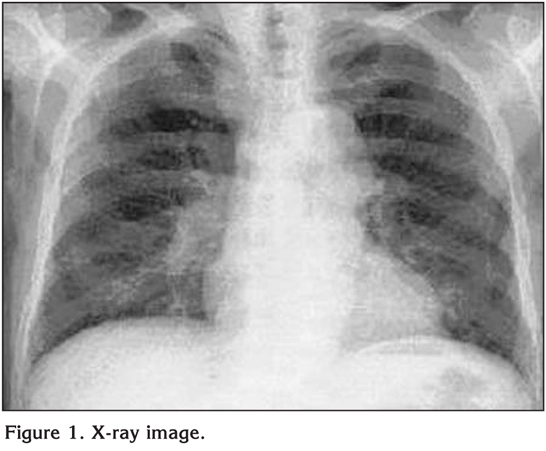

So the emergency doctors did not believe him. He had no abnormal sonority in both lungs at physical examination. He did not have fever showing signs of infection and he was very calm. The chest X-ray was normal (Figure 1). And the emergency doctor has convinced him that he didn't have any problems.

Figure 1

He applied to thoracic surgeon policlinic the day after. Physical examination and X-ray was normal again. But CT of the thorax revealed foreign body in left main bronchus (Figure 2). This foreign body was seen as long tube in his left main bronchus. But it was not blocking the air-way passage. A topical aerolized lidocaine spray and sedoanalgesia was performed to the patient. The trachea and left main bronchus was observed by RB. The tracheostomy canula had taken the shape of the left main bronchus. The forceps had been introduced through the RB to grasp gently the object for retrieval. Therefore, the RB, forceps and the tracheostomy canula were removed as a single unit. It was quite surprising to discover the silicone tracheostomy canula (Figure 3). The patient tolerated the procedure unexpectedly well and was discharged the following day.